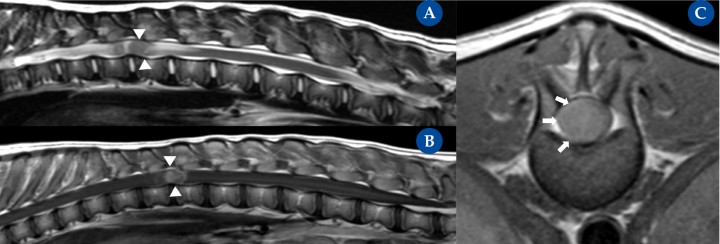

Tumor intramedular (nefroblastoma). Resonancia magnética: plano sagital ponderada en T2 (A), ponderada en T1 post contraste (B) y transversal ponderada en T1 post contraste (C) en un bulldog americano, de 5 meses de edad, hembra entera, con una historia crónica progresiva, de 6 semanas de evolución, de ataxia generalizada propioceptiva en ambos miembros pélvicos y paraparesia ambulatoria severa. La resonancia magnética mostró una masa intramedular (aunque inicialmente no se pudo descartar un componente intradural) a nivel de T12-T13 con realce focal y homogéneo tras la administración de contraste. La masa ocupa la casi totalidad del área de la médula espinal. En la secuencia de T2 se aprecian cambios intramedulares craneal y caudal a la masa intramedular compatible con edema medular. La posterior necropsia de la paciente confirmó la existencia de un nefroblastoma intramedular.